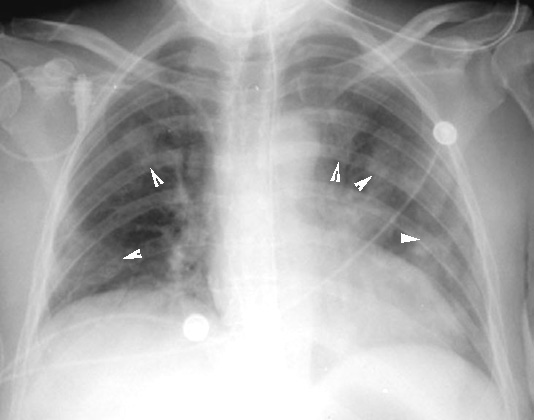

Aspergillosis: Invasive form

Arrowheads point to infarcts from angioinvasive aspergillosis.